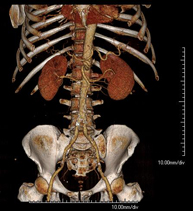

- Abdominal aorta CT angiography

A non-invasive diagnostic test that involves studying the abdominal aorta by obtaining high-definition anatomical images using CT (computed tomography) equipment and iodinated contrast. With the aid of workstations specialised for arterial studies, the image quality supports 2D and 3D reconstructions. It is indicated in patients with vascular disease (atherosclerosis), aortic aneurysms, abdominal pain of possible vascular origin, pre-surgical studies of lesions adjacent to the abdominal aorta as a vascular ‘map’, etc. Information obtained non-invasively is indispensable for patients requiring percutaneous or surgical processing. In patients who only require tracking of vascular lesions, this technique is the non-invasive technique of choice, together with MRI angiography.

- Renal artery CT angiography

A non-invasive diagnostic test that involves studying the renal arteries by obtaining high-definition anatomical images using CT (computed tomography) equipment and iodinated contrast. With the aid of workstations specialised for arterial studies, the image quality supports 2D and 3D reconstructions. This test is recommended, for example, in patients suffering from refractory hypertension that does not respond to processing, in patients with kidney damage in order to obtain a pre-surgical ‘vascular’ map, etc.

- Aortoiliac CT angiography

A non-invasive diagnostic test that involves examining the iliac arteries and abdominal aorta, obtaining high-definition anatomical images using CT (computed tomography) equipment and iodinated contrast dye. With the aid of workstations specialised for arterial studies, the image quality supports 2D and 3D reconstructions. This test is particularly recommended as a pre-surgical study (vascular map) prior to percutaneous or surgical interventions on the abdominal aorta, as a complementary study in patients with lower limb ischaemia, etc.